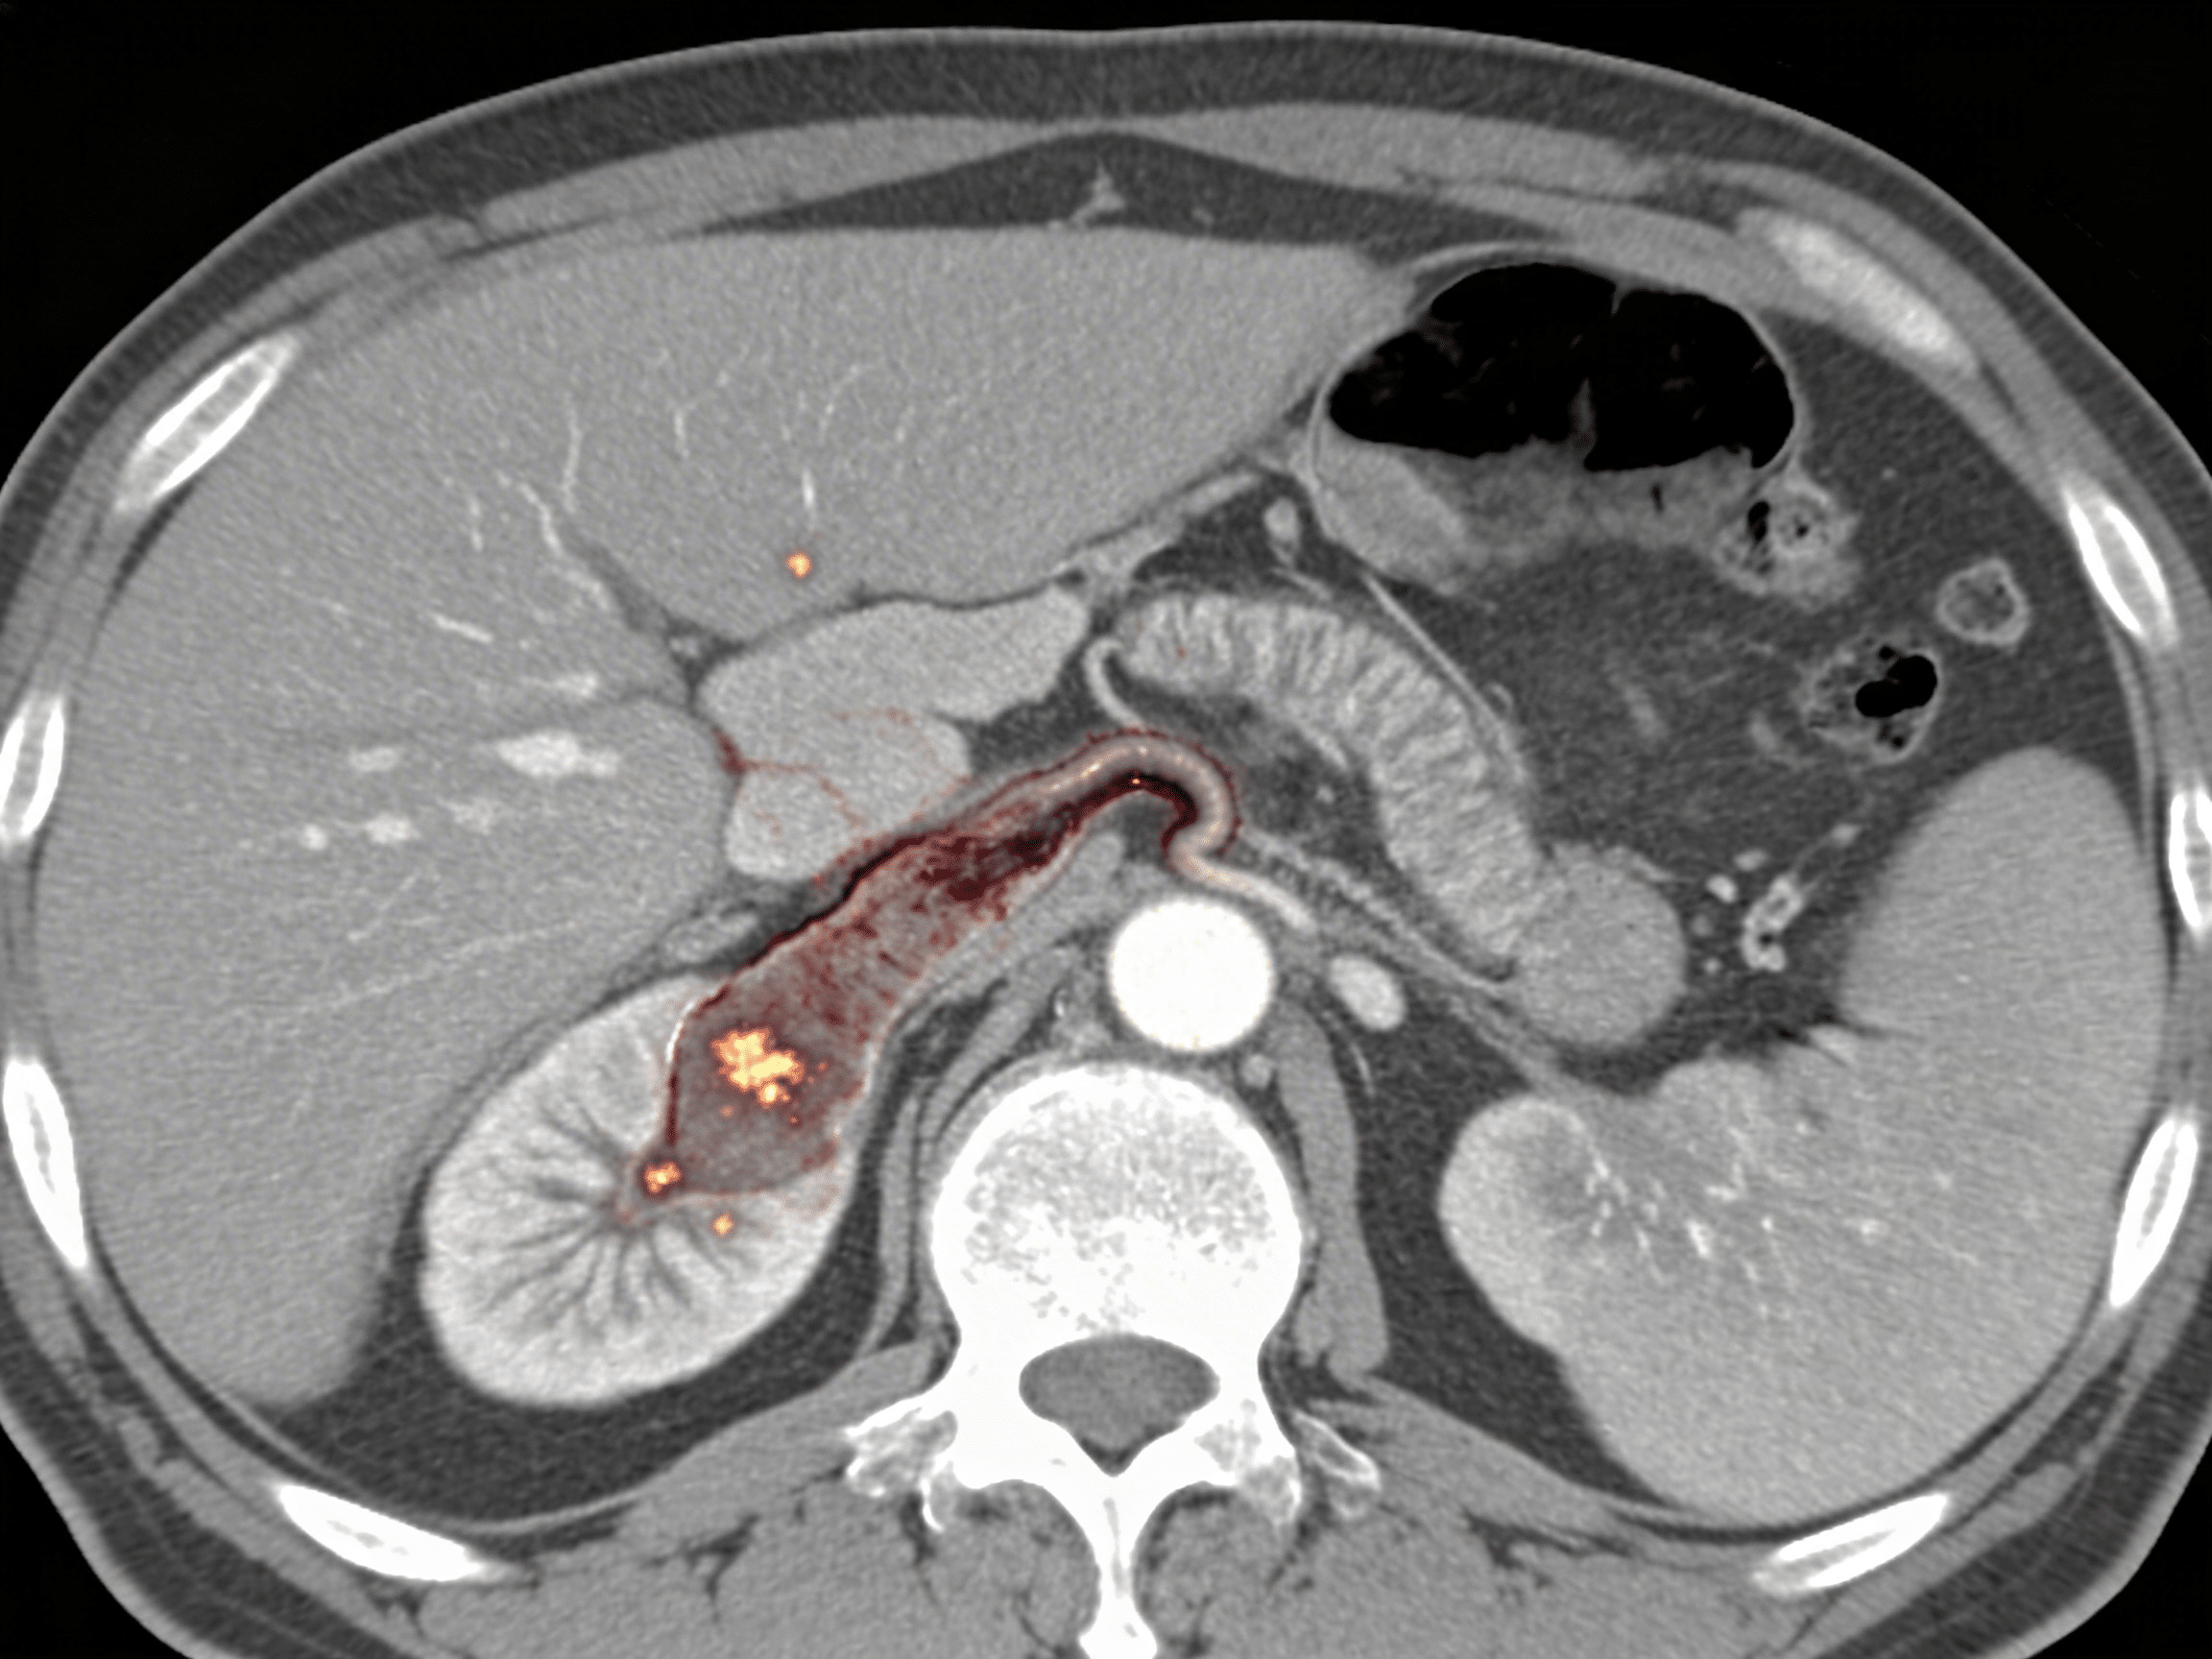

Can abdominal CT detect internal bleeding from trauma?

Yes, contrast-enhanced abdominal CT detects internal bleeding with 98% sensitivity, identifying solid organ injuries (liver, spleen, kidney lacerations), active arterial bleeding appearing as contrast "blush" or extravasation, and bowel or mesenteric injuries. Priority ER emergency physicians use AAST organ injury scales grading injury severity determining conservative management with serial hemoglobin checks versus immediate surgery or angioembolization. Free fluid without solid organ injury suggests bowel perforation or mesenteric injury requiring emergency exploratory laparotomy preventing peritonitis and sepsis from delayed diagnosis.

Priority ER's diagnostic capabilities for abdominal CT for suspected appendicitis, perforation, or internal bleeding exceed Joint Commission standards for emergency departments[14], featuring 64-slice multidetector CT scanner providing immediate high-resolution abdominal imaging with arterial, portal venous, and delayed phases identifying appendicitis (sensitivity 95%, specificity 94%), bowel perforation showing extraluminal air or oral contrast, and active arterial bleeding appearing as contrast extravasation requiring angioembolization[15]. Our emergency physicians trained in abdominal CT interpretation identify McBurney's point tenderness correlating with CT findings, periappendiceal fat stranding indicating inflammation, appendicolith suggesting obstruction, and appendiceal diameter >6mm confirming appendicitis requiring surgical consultation within hours preventing perforation.

Advanced imaging through our comprehensive diagnostic capabilities provides CT enterography protocols for small bowel evaluation, rectal contrast administration when pelvic abscess or appendiceal perforation suspected, and immediate interventional radiology consultation when CT identifies active arterial extravasation requiring angiography and coil embolization as alternative to surgery. For trauma patients, our emergency physicians utilize American Association for Surgery of Trauma (AAST) organ injury grading scales determining which solid organ injuries require operative management versus nonoperative observation with serial imaging and hemoglobin monitoring. This comprehensive approach explains why the American College of Radiology appropriateness criteria mandate CT as first-line imaging for suspected appendicitis in adults, replacing ultrasound and clinical diagnosis alone improving diagnostic accuracy from 80% to 98%.